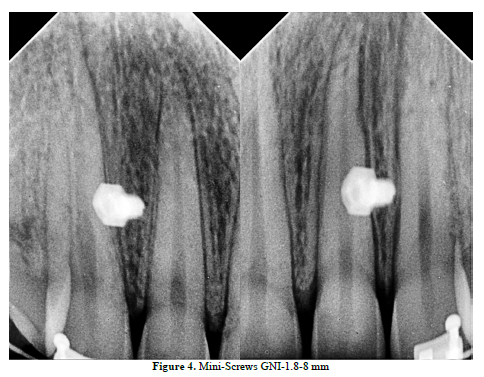

The solution of TADs has improved the aesthetic appearance, the patient’s smile and even the patient’s Cupid’s bow “Smile Arc”, Figure 4, 5.

TADs are of a paramount importance within treatment of scissors-bites (Figure 9,10), scheming the treatment plan is supposed to include the TADs pulling (Figure 11,12 & 13).